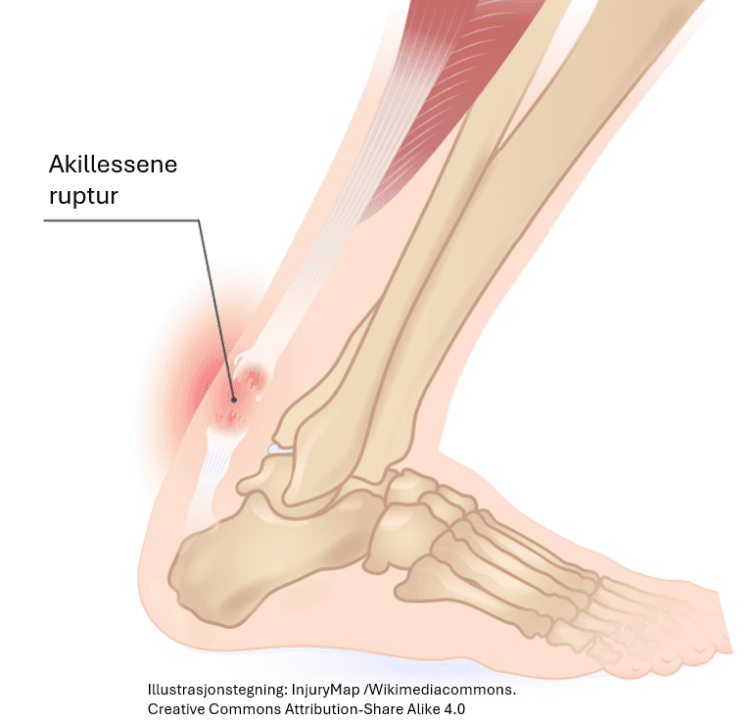

Musklene som beveger skjelettet, er festet til benene via sener. En muskel eller sene kan bli strukket eller overrevet. Denne typen skade skjer ofte nær overgangen mellom muskel og sene. Det kan være bare noen få eller det kan være mange muskelfibre som er overrevet - ja, det hender at hele senen kan rives over, f.eks. avrevet akillessene (akillessene ruptur). Slike skader forårsaker kraftig blødning i området. Siden blødningen skjer dypt i vevet, blir den ikke alltid synlig, men den kan gi sterke smerter og ubehag. En overrevet muskel eller sene trenger vanligvis lang tid på å tilhele.